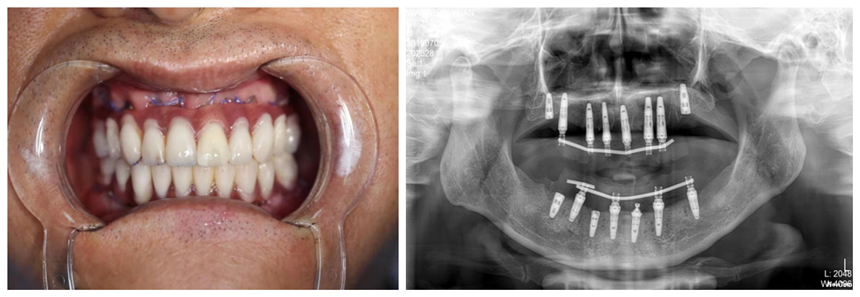

由于全口種植技術(shù)要求較高,患者王先生的骨條件又不理想,醫(yī)生在術(shù)前利用王先生的牙齒模型和CBCT數(shù)據(jù),為其制作了數(shù)字化種植手術(shù)導(dǎo)板,使手術(shù)更微創(chuàng)、更。從開始拔牙、種植到制作臨時(shí)義齒,再到后佩戴調(diào)試完畢,口腔科種植團(tuán)隊(duì)整整用了12小時(shí)。當(dāng)王先生看到自己的一口新牙時(shí),露出了滿意的笑容,開心地說:“一天的辛苦是值得的!謝謝你們,我終于有一口好牙啦!”

術(shù)后片